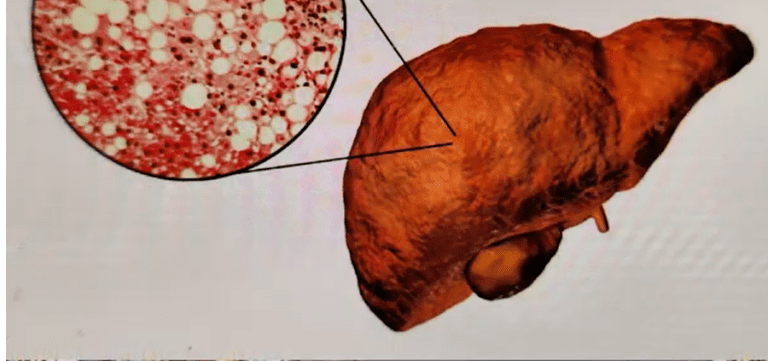

Why do doctors do Liver Function Tests?- By Dr harold Gunatillake

Why do doctors do Liver Function Tests?- By Dr harold Gunatillake Liver function tests are blood tests used to help...